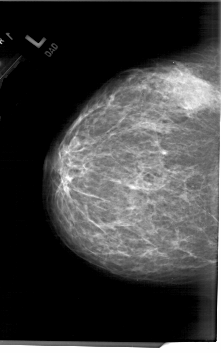

A_1779_1.LEFT_CC

LEFT_CC LINES 6706 PIXELS_PER_LINE 4186 BITS_PER_PIXEL 12 RESOLUTION 43.5 NON_OVERLAY